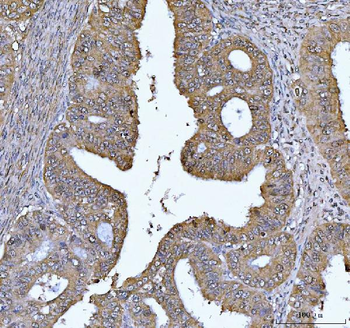

FEN1 Antibody

Catalog Number: orb193665

| Description | FEN1 Antibody |

| Tested applications | IF, IHC, WB |